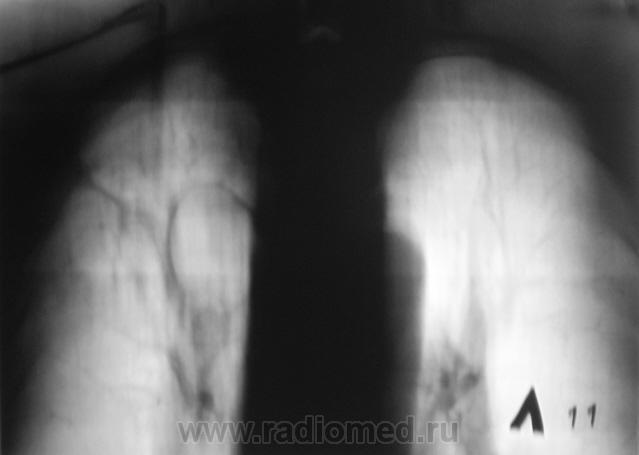

Контроль после флюорографии.

Произведено стандартное дообследование.

Процесс свежий. Но, вот кисты справа в верхней доле были, и ранее.